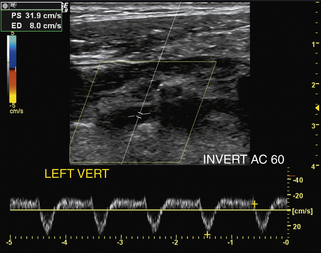

У пациентов с доминирующей позвоночной артерией недоминирующая, анатомически маленькая позвоночная артерия может демонстрировать характеристики кровотока с повышенным сосудистым сопротивлением со снижением скорости кровотока на пике систолы и во время диастолы. В более тяжелых случаях гипопластической, атретичной (диаметр просвета менее 2 мм) позвоночной артерии, которая может встречаться у 15% пациентов, сосудистое сопротивление по ходу сосуда может быть настолько повышено, что спектральная допплеровская волна приобретает характеристики почти полной дистальной окклюзии (т.е. отсутствие обнаруживаемого диастолического потока; рис. 11-14 ). Тяжелая обструктивная болезнь проксимальных отделов позвоночных артерий также может быть причиной снижения кровотока в вертебробазилярной системе и цереброваскулярных симптомов. В таких случаях форма волны спектральной допплеровской скорости демонстрирует форму волны tardus-parvus, характерную для затухания, форму волны с задержкой начала округлого, плохо выраженного систолического пика, плохой антеградный поток во время диастолы и значительное снижение скорости на протяжении всего сердечного цикла (рис . 11-15 ). Если в позвоночной артерии наблюдаются затухающие допплеровские сигналы, необходимо провести тщательное дуплексное ультразвуковое исследование проксимального сегмента и места расположения пораженной позвоночной артерии, чтобы определить локализацию и тяжесть любого обструктивного поражения, которое может присутствовать.

РИСУНОК 11-15. Уменьшение кровотока в средней позвоночной артерии вследствие проксимального стеноза. Кривая скорости имеет классическую форму tardus-parvus с округлым, плохо выраженным систолическим пиком и снижением скорости на протяжении всего сердечного цикла. (Пиковая систолическая скорость [ПСВ] составляет 13 см/сек.)